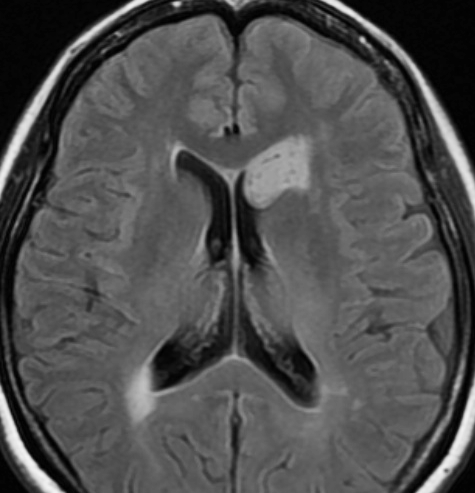

無症状で偶然発見された47歳女性の側脳室内上衣下腫

無症候で偶然発見された左側脳室前角尾状核頭に接したsubependymoma。定位脳生検で病理診断を得たましたが,3年間の観察で徐々に増大しました。左上が発見時,1年後(右上),2年後(左下),3年後(右下)

CTではやや低吸収,T1ガドリニウムでは低信号となりガドリニウム増強されません。小さな上衣下腫の場合は等吸収あるいは等信号のものも多いです。小さく点状に造影されている部分があるがこれは定位脳手術痕(track)です。

左中前頭回からの経皮室法 left middle frontal gyrus transcortical approach で全摘出できました(右図)。